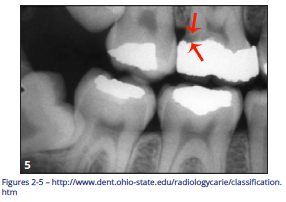

Secondary or Recurrent Caries (Figure 5)

Includes caries seen adjacent to or beneath an existing restoration.

Figure 5